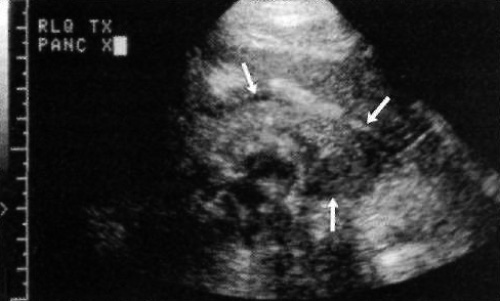

Поджелудочную железу пересаживают вместе с частью двенадцатиперстной кишки. Чревная и верхняя брыжеечная артерии остаются прикрепленными к части аорты донора. Артерии анастомозируют с общей подвздошной артерией, а место слияния воротной вены – с соответствующей подвздошной веной. Чтобы обеспечить отток секрета экзокринной части поджелудочной железы, петлю двенадцатиперстной кишки анастомозируют с толстой кишкой или (редко) с мочевым пузырем (фото 1 и 15).

Фото 15. Трансплантат поджелудочной железы. Стрелками обозначена нормальная конфигурация трансплантата поджелудочной железы, локализованного в нижнем квадранте. Скопление жидкости не определяется